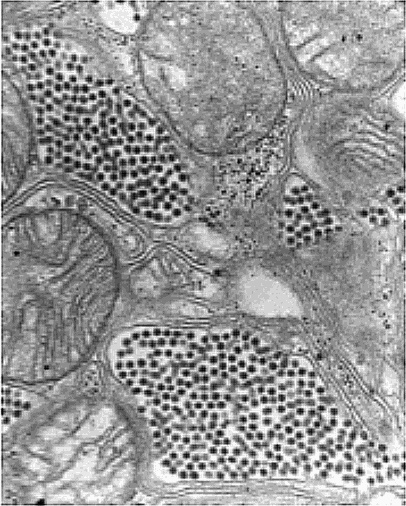

– Лиза, позвольте ввести вас в курс дела. На предыдущем совещании я говорил о том, что, как мне показалось, нам удалось мельком взглянуть на то чудовище, с которым мы имеем здесь дело. Вот снимок поперечного среза альвеолы легкого инфицированной крысы.

Иллюстрация к книге — Шестое вымирание [_08.jpg]

Лиза прильнула к экрану, изучая скопления крошечных частиц, плотно заполнивших маленькие воздушные клетки легкого.

– Это определенно похоже на вирионы – внеклеточные вирусные частицы, – согласилась она. – Но я никогда не видела ничего столь крошечного.